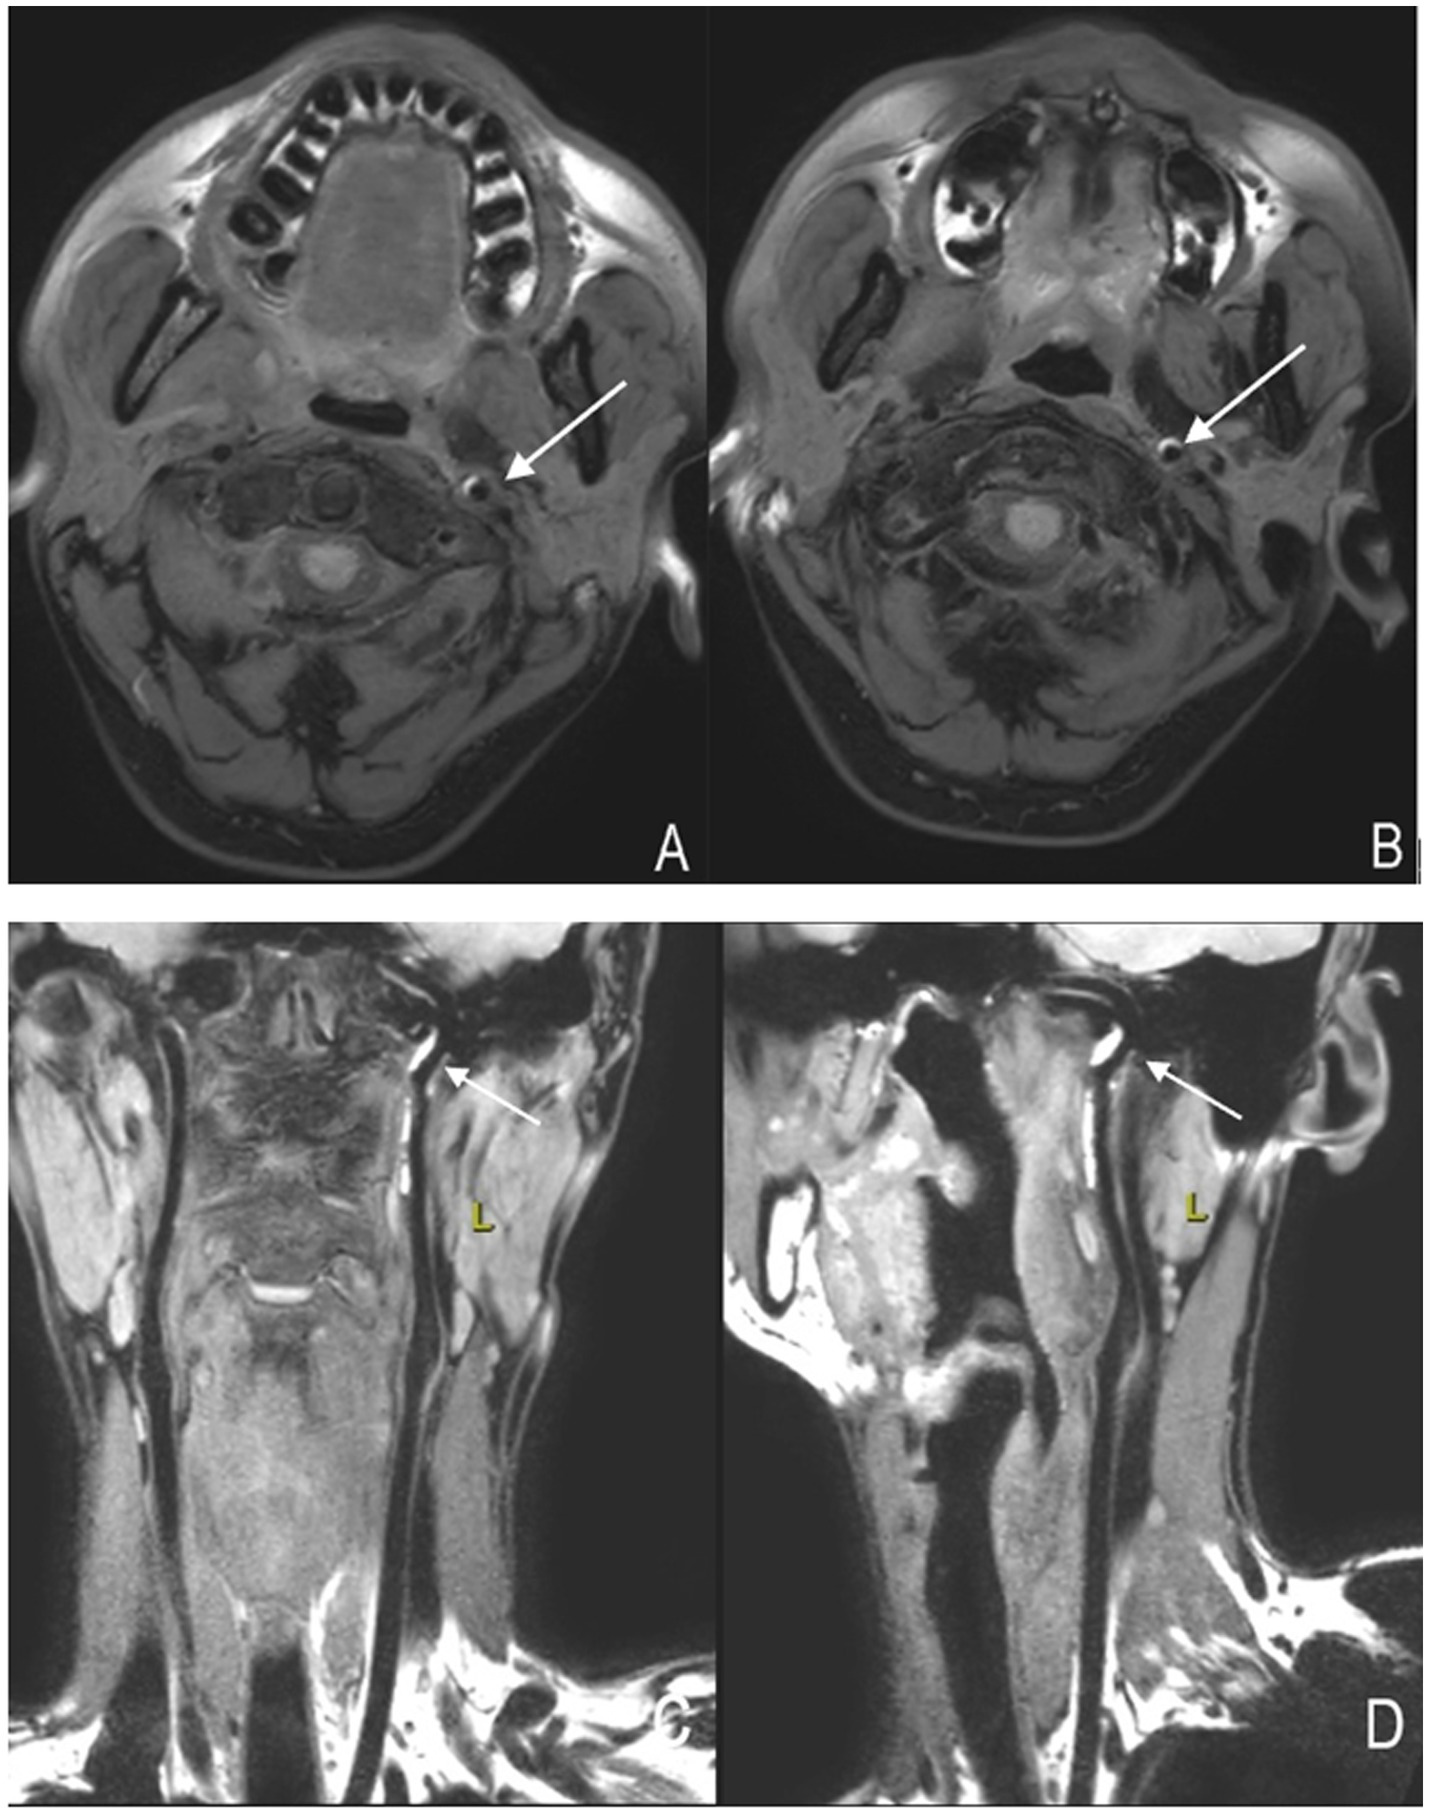

High-resolution magnetic resonance imaging vessel wall imaging technology, based on black-blood imaging sequences, employs presaturation pulses to suppress intraluminal blood flow signals, enabling clear visualization of cervical artery wall and lumen structures, significantly improving the detection rate of intramural hematomas (22, 30–33) (Figure 3). Research indicates that high-resolution MRI vessel wall imaging not only clearly visualizes collapsed vascular walls with occlusive thrombi and occlusion lengths in cases of cervical artery occlusion but also demonstrates better consistency with DSA in detecting tandem lesions and chronic occlusions of the internal carotid artery (ICA) (34, 35). Moreover, high-resolution vessel wall imaging holds significant value in early risk assessment and prognostic follow-up of CAD patients. Wu et al. (36) found that irregular surfaces and intraluminal thrombi on high-resolution imaging correlate with stroke occurrence in patients with cervical-carotid artery dissection (CCAD). Lee et al. (37) demonstrated that HR-MRI enables tracking of hematoma absorption processes and predicts dissection vessel recanalization based on changes in intramural hematoma signals. Hashimoto et al. (33) further emphasized that the temporal sequence signal characteristics of T1-weighted vessel wall imaging for intramural hematomas may serve as diagnostic imaging biomarkers for spontaneous healing within 3 months post-VAD onset. Additional studies report that HR-MRI vessel wall imaging outperforms DSA in diagnosing vertebral artery dissection (38). Given HR-MRI's superior visualization of vessel walls and demonstrated prognostic follow-up advantages, it is currently considered the most promising imaging modality for CAD diagnosis (39).

Figure 3

High-resolution magnetic resonance imaging showing arterial dissection-related vascular changes. (A,B) Axial images of the left internal carotid artery. The crescent-shaped high signal indicated by the arrow represents an "intramural hematoma." (C,D) Coronal and sagittal images of the left internal carotid artery, respectively. The high-signal structure indicated by the arrow represents an "intramural hematoma".